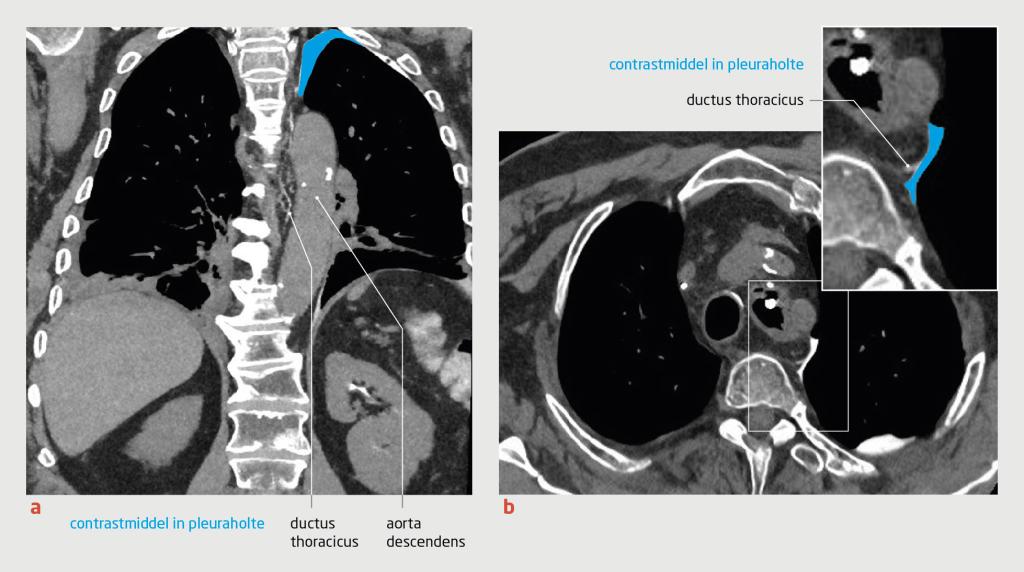

Om het punt van lekkage beter in beeld te krijgen werd intranodale CT-lymfangiografie verricht. Daarop was te zien dat het lek zich hoog in het mediastinum bevond (figuur 3). Vervolgens bracht de interventieradioloog lipiodol in via de intranodale techniek, omdat directe canulatie van de ductus en ‘coilen’ niet lukte. In de daaropvolgende dagen nam de chylothorax significant af en herstelde de patiënt zodanig dat hij naar huis ontslagen kon worden.